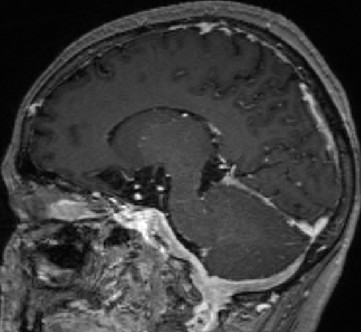

2013-5-16 MRI